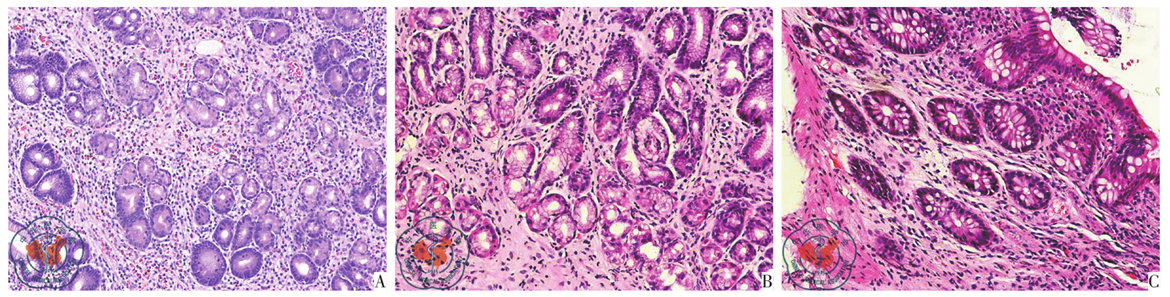

图1 图A为胃角活检20×,黏膜固有层见较多嗜酸性粒细胞浸润,最多约100个/HPF;图B为胃角活检20×,黏膜固有层未见明显嗜酸性粒细胞浸润;图C为横结肠活检20×,黏膜固有层未见明显嗜酸性粒细胞浸润